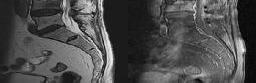

Preoperative MRI images are shown from a 67-year-old woman with neck pain, bilateral upper extremity paresthesias, progressively worsening balance, several falls, and increasing problems in both hands with dropping objects. Figure 1 is a sagittal view, Figure 2 is an axial cut at C2-3, Figure 3 is an axial cut at C5-6, and Figure 4 is an axial cut at C6-7. The patient’s motor strength is grade 4+ of 5 in the bilateral upper extremities.

What is the best next step?

4. Posterior decompression and fusion Discussion: D

The patient has degenerative changes with central and foraminal stenosis from C2-7, including spinal cord compression at C2-3, C5-6, and C6-7. Her progressively worsening balance, falls, and clumsiness are consistent with cervical spondylotic myelopathy. Given the progressive nature of the neurologic symptoms, surgery is recommended for patients with worsening

symptoms. Physical therapy potentially could provide pain relief but would not address the spinal cord compression. Cervical epidural steroid injection is not recommended because of the increased neurologic risk in the setting of substantial spinal cord compression. Given the multiple levels involved and the extension to the C2-3 level, an anterior approach would increase the risk of morbidity and pseudarthrosis compared with the posterior approach, which would allow adequate decompression of the central and foraminal stenosis.

Surgery for cervical myelopathy is performed to decompress the spinal cord, stabilize the spine, and prevent further neurologic injury. Most patients obtain considerable pain relief and some improvement in balance and clumsiness, depending on the severity of the symptoms. Complete resolution of all symptoms should not be expected.